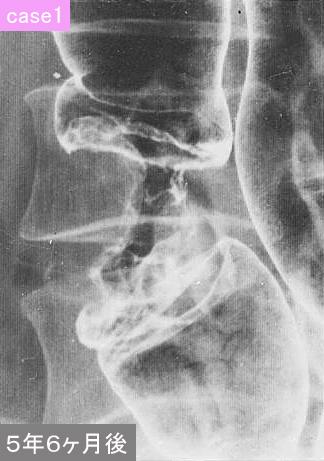

case1は1976年に切除された症例です。患者さんの問題を含めて種々の理由で、また複数の施設にて2回の注腸X線検査がなされましたものを集めて検討いたしました。いずれも医学上で、進行大腸癌への発育進展の解明に大いに寄与した例でしたので、提示いたします。

疾患(病理主体)の分類悪性上皮性腫瘍/腺癌

部位(臓器別)大腸/横行

検査方法X-P

腫瘍の肉眼分類2型(潰瘍限局型)/

病変の最大径(ミリ)40以上

腫瘍の深達度ss(a1)

多発腫瘍(同一臓器)有(異時性)

多重腫瘍(他臓器)有(異時性)